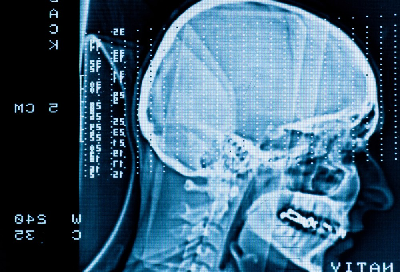

6. Восстановление мозга после кровоизлияния

Инсульт – еще одно сосудистое заболевание, делающее людей либо глубокими инвалидами, либо вообще отнимающее жизнь. Причем никто не знает, что хуже. Ведь человек после инсульта может быть полностью либо частично парализован, могут быть утрачены речь, слух, зрение, могут нарушиться интеллектуальные способности. За таким человеком очень тяжело и дорого ухаживать.Однако медики нашли спасение для таких больных в стволовых клетках. Их вводят прямо в мозг, после чего у человека восстанавливаются или улучшаются многие функции.